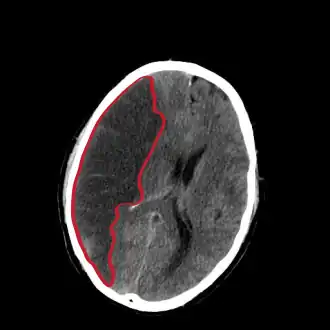

Компьютерная томограмма головного мозга, демонстрирующая инфаркт в правом полушарии головного мозга (зона инфаркта обведена красным.) | |

Ишеми́ческий инсу́льт (инфаркт мозга) — нарушение мозгового кровообращения с повреждением ткани мозга, нарушением его функций вследствие затруднения или прекращения поступления крови к тому или иному отделу. Может быть обусловлен недостаточностью кровоснабжения определённого участка головного мозга по причине снижения мозгового кровотока, тромбоза или эмболии, связанных с заболеваниями сосудов, сердца или крови[2]. Является одной из основных причин смертности среди людей[3].